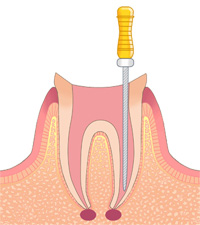

根管治療

歯の中心部に細菌が入り込むと、根管治療を行わなくてはなりません。根管治療には丁寧な施術が不可欠です。当院では、1回の治療に1時間以上かけて確実に行っています。

虫歯が進行して歯の中心にある歯髄部分にまで達してしまうと、根管治療が必要となります。しかし、この歯髄部分は非常に細く、曲がっています。その曲がり方も人によって違うので、きちんと治療するのは大変難しいのです。

歯髄に細菌が入り込んでしまうと、細菌によって腐ってしまった部分を取り除くだけでは終わりません。周囲の歯髄にも細菌が入り込んでいる可能性があるので、リーマーやファイルといった細い器具で、歯髄部分を全部掻き出す必要があります。

時間をかけて確実に治療

根管治療を行ったにも関わらず、しばらくするとまた歯が痛み出すことがあります。原因は、根管部分に細菌が残ってしまい、中で再び繁殖してしまったこと。その場合、歯に被せた冠を取って、根管治療をやり直します。

そういった事態を避けるためには、根管治療をしっかりと丁寧に行うしか方法はありません。当院では確実に歯髄を取り、徹底的に除菌するため、1回の根管治療に1時間以上かけてしっかりと行っています。症例によっては2時間近くかかることもありますが、確実な治療のためとご理解いただければ幸いです。

技術と経験で、患者さまの負担を軽減

根管治療は非常に難しく時間がかかる施術なので、通常は数回に分けて行われます。しかし、患者さまはそのために何度も通院しなければなりません。さらに、根管治療を行っている間は、その歯に被せ物をするわけにもいかないので、食事などにも不便です。

根管治療は非常に難しく時間がかかる施術なので、通常は数回に分けて行われます。しかし、患者さまはそのために何度も通院しなければなりません。さらに、根管治療を行っている間は、その歯に被せ物をするわけにもいかないので、食事などにも不便です。

当院では、そういった患者さまのさまざまな負担を考え、少ない治療回数で根管治療を終わらせています。当院のドクターは、今までに多数の症例を手がけてきた根管治療の専門家です。豊富な経験から培った確かなテクニックで、少ない治療回数で細菌に感染した部分を確実に取り去り、除菌します。

時間をかけた施術が必要な根管治療は、患者さまにとっても負担です。当院では経験から培われた確かな技術で、できるだけ少ない治療回数で根管治療を終わらせます。

みなさまは「根管治療」という言葉を聞いたことがありますか?歯の中心にある歯髄は管状になっていて、中には神経や毛細血管がとおっています。この管状の部分を根管と言います。虫歯が進行して歯の中心部である歯髄にまで達してしまったとき、あるいは歯の根の病気にかかったときに、根管治療が必要となります。

しかしこの根管治療は難しく、時間もかかります。なぜ根管治療はそれほど難しいのでしょうか。

時間のかかる根管治療

根管の中はとても細いので、直接目で見ることができません。しかも根管の形はまっすぐではなく、人によってそれぞれ曲がり方が違います。そのため内部に細菌が入ってしまうと、きれいに取り除くことが難しくなってしまうのです。

たとえ根管治療を行っても、中に細菌が残ったまま詰め物や被せ物をすると、歯の内部で細菌が増殖して新たなトラブルを引き起こしてしまいます。そのため、細菌を取り除くためには時間をかけて丁寧に治療するしかありません。場合によっては、患者さまは何度も歯科医院に通うことになってしまうのです。

少ない回数で治療を終わらせる技術と経験

当院では、さまざまな面から患者さまの負担を考え、できるだけ少ない治療回数で根管治療を終わらせています。症状によっては、1回で終わらせることも可能です。ただし、1回の診療にかかる時間は1時間以上と、ちょっと長めです。

当院では、さまざまな面から患者さまの負担を考え、できるだけ少ない治療回数で根管治療を終わらせています。症状によっては、1回で終わらせることも可能です。ただし、1回の診療にかかる時間は1時間以上と、ちょっと長めです。

当院のドクターは、根管治療の症例をいくつも手がけてきた専門家です。確かな技術と豊富な経験から、少ない治療回数で、細菌に感染した部分を再発しないようにきちんと取り去り、除菌します。何回にも分けて根管治療を行うと、治療の間に残った細菌が繁殖してしまうことがあります。そのため、少ない回数で治療を終わらせることがベストなのです。